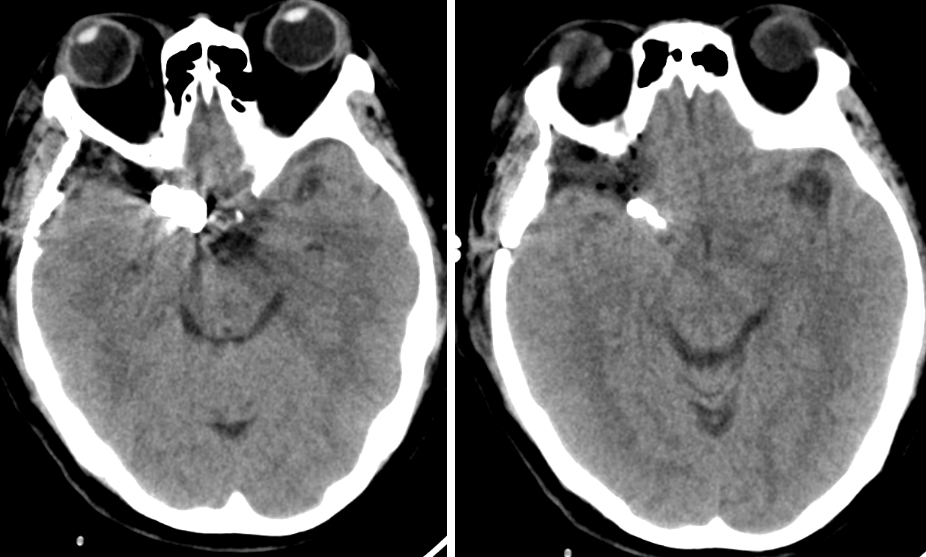

头颅CT

术后第1天CT

术后第1天CTA

患者术后病情稳定,神清,语明,双侧瞳孔等大等圆,直径约2.5mm,光反应灵敏,视力及视野正常,四肢肌力、肌张力正常。